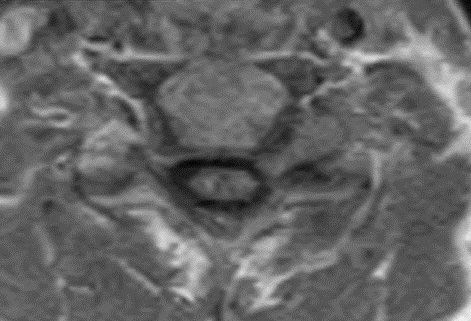

This patient underwent a second limited contrast examination. Pre- and post-contrast T-1 weighted images were obtained. Fig. 4 represents the pre-contrast T-1 weighted image, and Fig. 5 represents the post-contrast image at the same level. There is a quite definite increase in signal intensity of the mass on the post-contrast images. Thus, the mass is said to enhance and this is indicative of a neoplastic process. The most common extradural intraforaminal mass is a schwannoma, which represents a nerve sheathe tumor. This was the presumptive diagnosis as the patient underwent surgery for removal of the tumor. Subsequent biopsy of the lesion confirmed schwannoma. The patient did well post- surgery and the left upper extremity symptoms resolved.